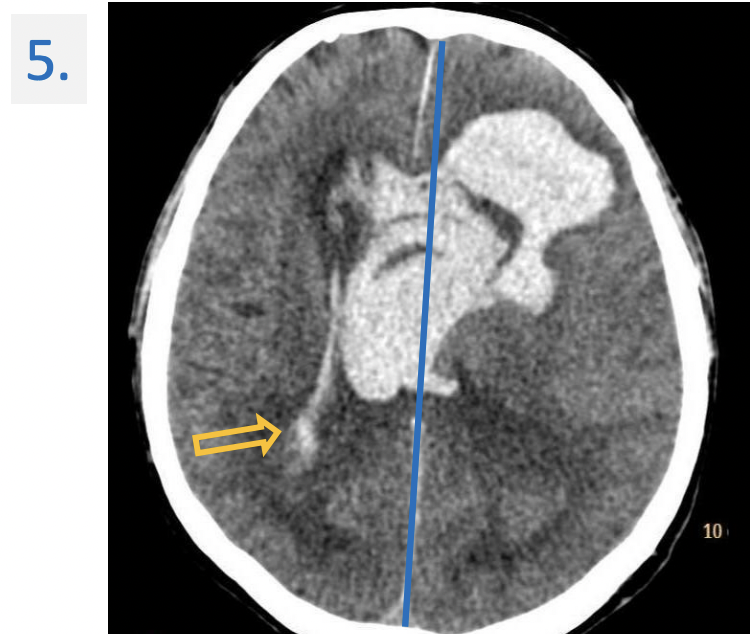

5.